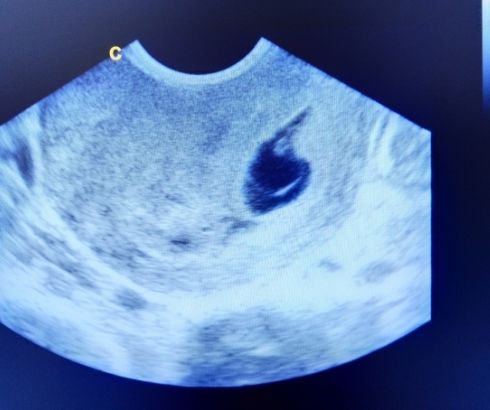

4 Weeks Pregnant Ultrasound

Ultrasound at the 4th week is not prescribed without good reason. An ultrasound examination will normally be scheduled somewhere around 12-14 weeks and further according to the plan. An examination may be ordered earlier if there are bad symptoms or multiple pregnancy is suspected.

The examination will not yet be able to give specific details regarding the development of the embryo. It makes sense to study to exclude any pathologies.

- Presence of one or more fertilized eggs

- Exclude the presence of ectopic pregnancy

- Assess the condition of the endometrium

- Assess the condition of the vessels of the pelvic organs

- Rule out uterine pathology

More accurate and detailed details of the ultrasound examination can be expected later in pregnancy. You can only confirm the fact of your position.